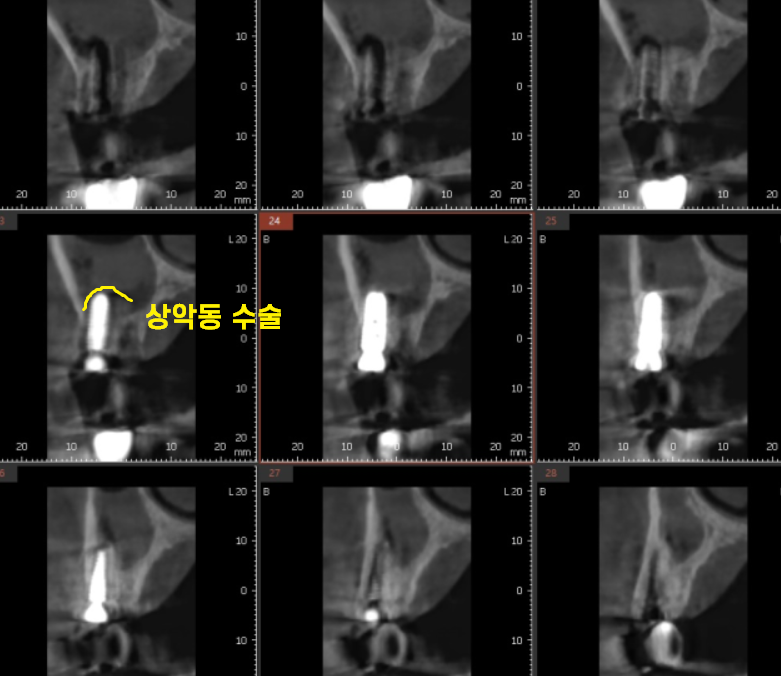

흔들리는 치아 2개를 발치 후

상악동을 들어 올려 뼈 이식을 하는

수술까지 같이 진행해드렸는데요

▼상악동 거상술이란 ??▼

이전 글에서 언급해드렸듯

상악동 거상술이 잘된 임플란트는

돔 형태로 올라간 것을 확인하실 수 있습니다.

오늘의 환자분도

상악동 막이 예쁘게 잘 올라갔네요